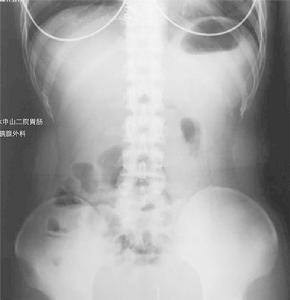

X光片遺傳易感性

②X線表現有胃腸道裂隙狀潰瘍、鵝卵石征、假息肉、多發性狹窄、瘺管形成等。病變呈節段分布。CT可顯示腸壁增厚的腸襻,盆腔或腹腔的膿腫。